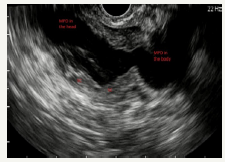

SCN is a cystic neoplasm filled with serous fluid, originating from centroacinar cells and consisting of cubic glycogen-rich cells [10]. SCN is more common in women, most often in the sixth - seventh decade of life (50-60 years) [12]. The median age is 68 years [45]. Due to its benign nature, such tumors can grow to large sizes, without any symptoms [46]. Usually SCN is a single cyst, of a rounded shape, consisting of many small cysts, ranging in size from millimeters to several centimeters. The presence of microcystic component is called the sign of “honeycomb”, which is characteristically of this type of neoplasm [47] (Figure 9A-9C). Often in the center of the tumor can be located fibrous scar [12,25,33]. The inner surface of the cyst is lined with a single layer of cubic epithelium. The outer wall and the inner septs of the tumor of a good blood supply. SCN does not communicate with the pancreatic duct. The cyst is filled with a clear serous fluid.

Figure 9A:Clinical case of SCN in 42 years old woman.

Figure 9B:EUS view of the neoplasm (in the red oval). On EUS imaging we can very well see “honeycomb” sing.

Figure 9: Clinical case of SCN in 42 years old woman.